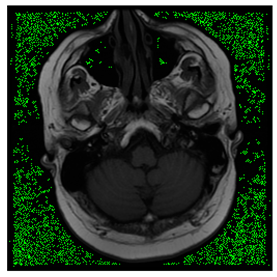

Breast-MRI-NACT-Pilot is an MRI-type image database, collecting breast medical images of 64 patients. Some samples are shown in Figure 12a.

Figure 12.

Sampled images in the tested benchmark databases: (a) Breast-MRI-NACT-Pilot (breast), (b) ACRIN-DSC-MR-Brain (brain), (c) NIH (chest), (d) Lung-PET-CT-Dx (lung), (e) Prostate-MRI (prostate), and (f) Other grayscale standard images.

ACRIN-DSC-MR-Brain database contains MRI-type and CT-type brain medical images. Some samples are shown in Figure 12b.